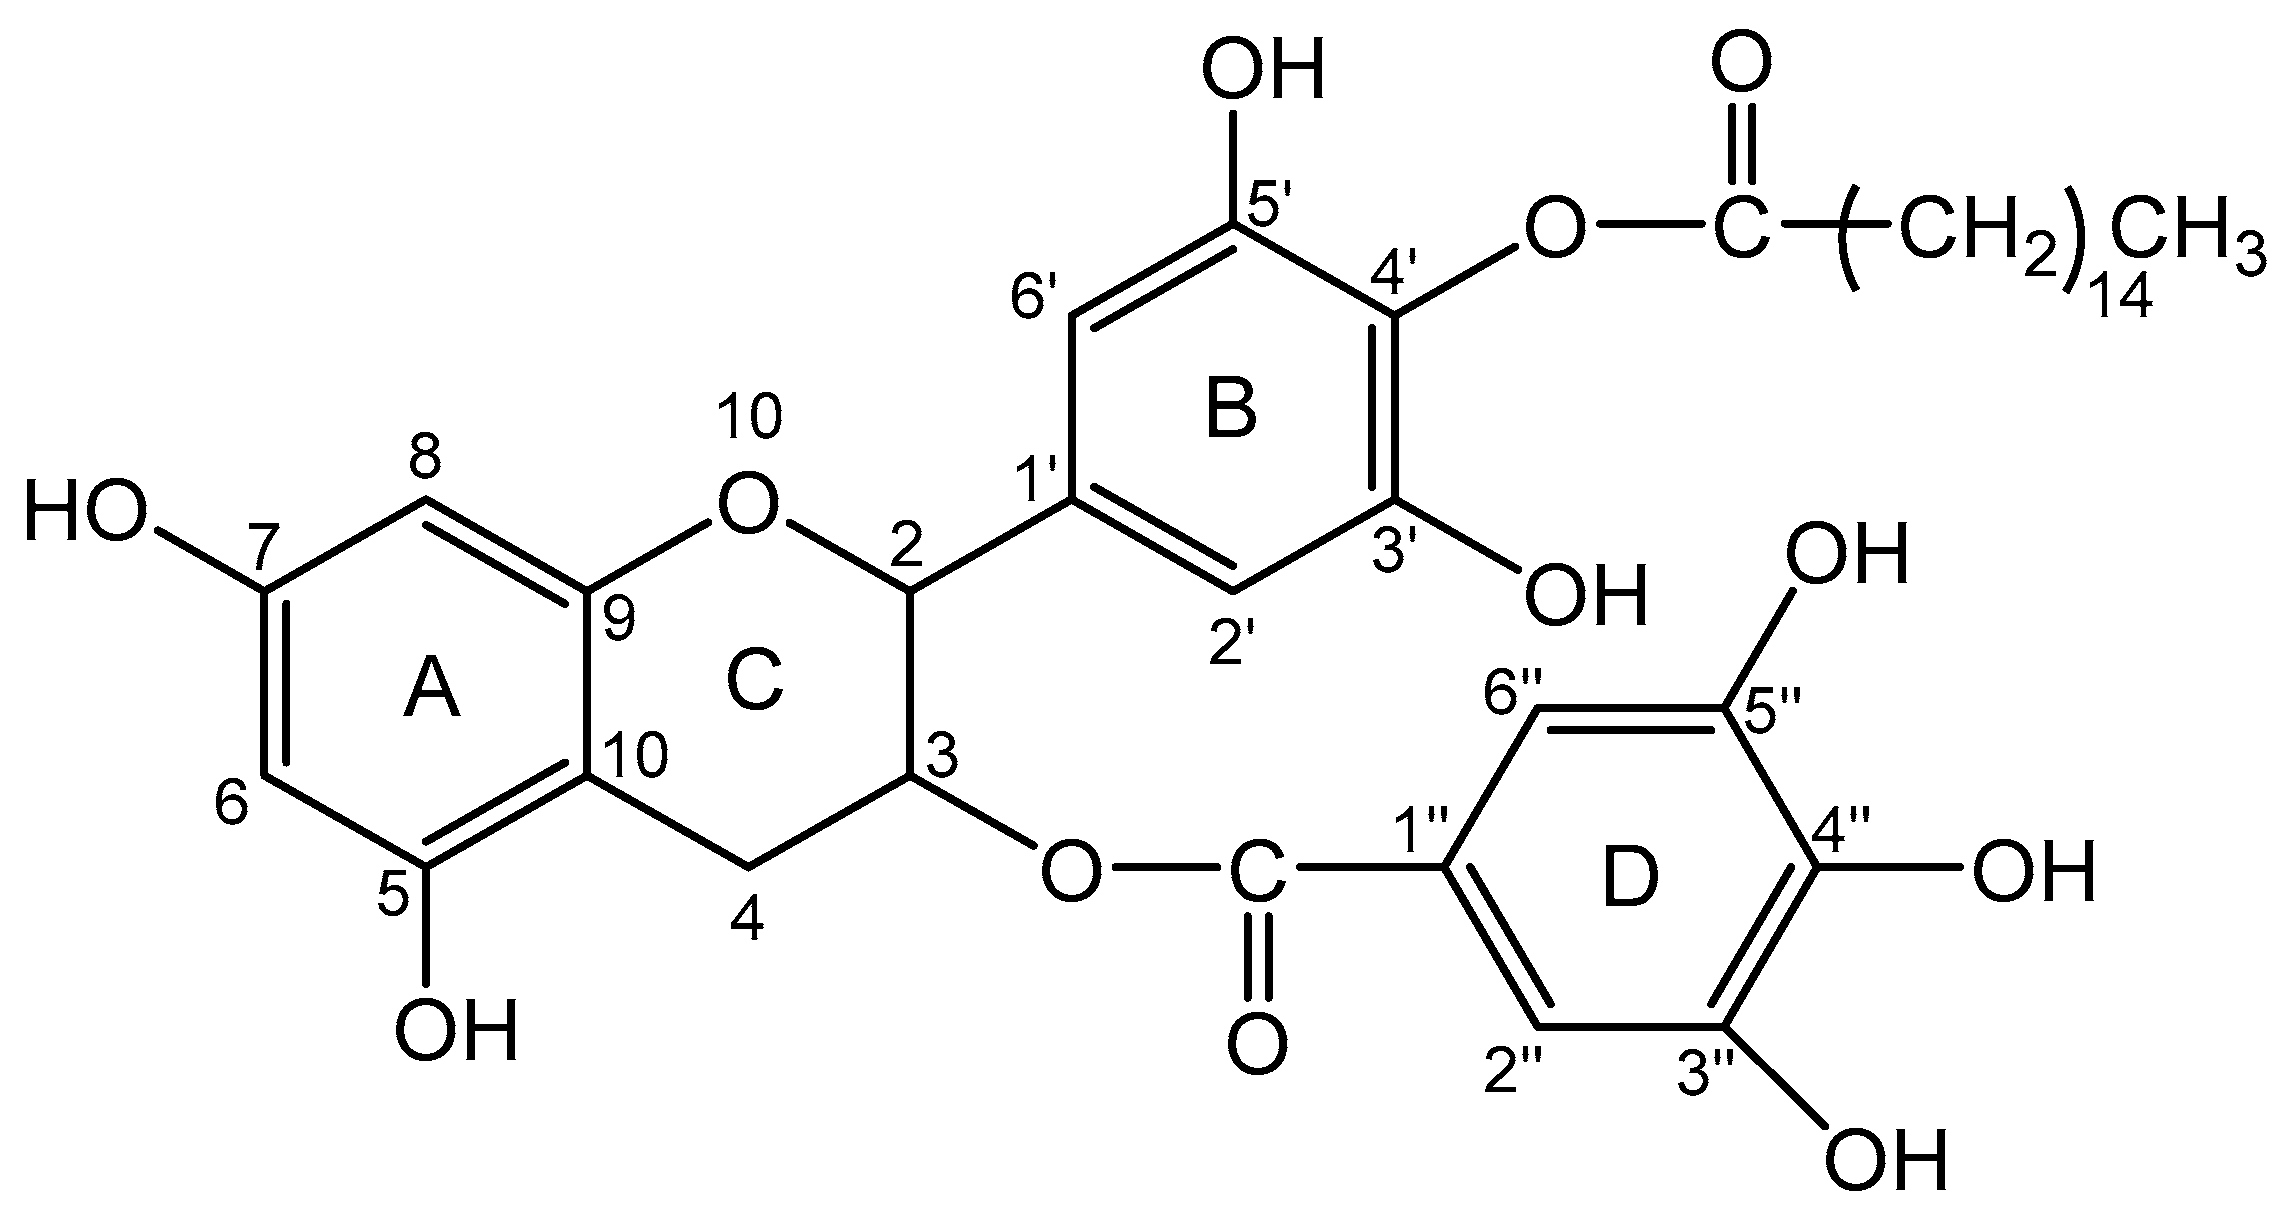

2.2. EC16, EC16m, and Other Supplies

2.3. EC16 and EC16m Nanoformulations